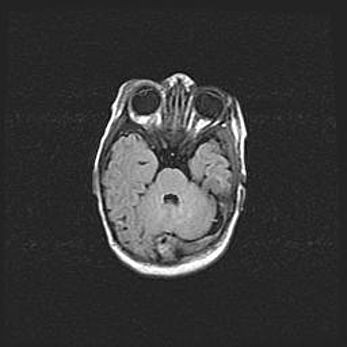

Сообщающаяся гидроцефалия. Кистозная энцефаломаляция головного мозга.

Возраст: 3 месяца 4 дня

Вес: 3100 г

Пол: женский

Окружность головы: 34 см

Срок гестации: 31 неделя

Кистозная энцефаломаляция головного мозга - одна из форм поражения головного мозга в детском возрасте. Характеризуется возникновением множественных и распространённых кист в коре, белом веществе и подкорковых образованиях головного мозга у плодов, новорождённых и детей раннего возраста. Развитие кистозной энцефаломаляции связано с внутриутробной асфиксией и гипотонией, родовой травмой, тромбозом синусов, пороками развития сосудов, инфекциями, сепсисом и другими причинами. Наиболее значимые инфекционные агенты: вирусы простого герпеса, цитомегалии, краснухи, токсоплазмы, энтеробактерии, золотистый стафилококк и другие.